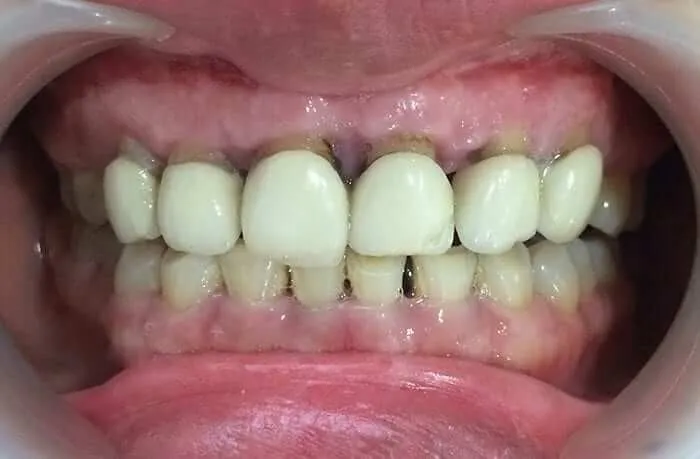

Hiện tượng răng sứ bị hở là hiện tượng rất nhiều người gặp phải. Tuy nhiên, rất ít người nhận ra được cho đến khi nó trở